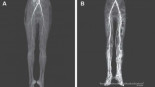

Diagnostican a una mujer con ardor en las piernas la enfermedad medieval del "fuego del infierno"

Un caso publicado en The New England Journal of Medicine informa de la llegada de una joven de 24 años a una clínica dos días después de que comenzara a sentir una sensación de ardor en las piernas que se extendía desde los dedos de los pies hasta la mitad de los muslos. Los doctores le diagnosticaron ergotismo, “fuego del infierno” o “fuego de San Antonio”, una enfermedad muy común en la época medieval. Tradicionalmente se producía por el hongo ergot o Claviceps purpurea en centeno infectado y otros cereales básicos en Europa continental.